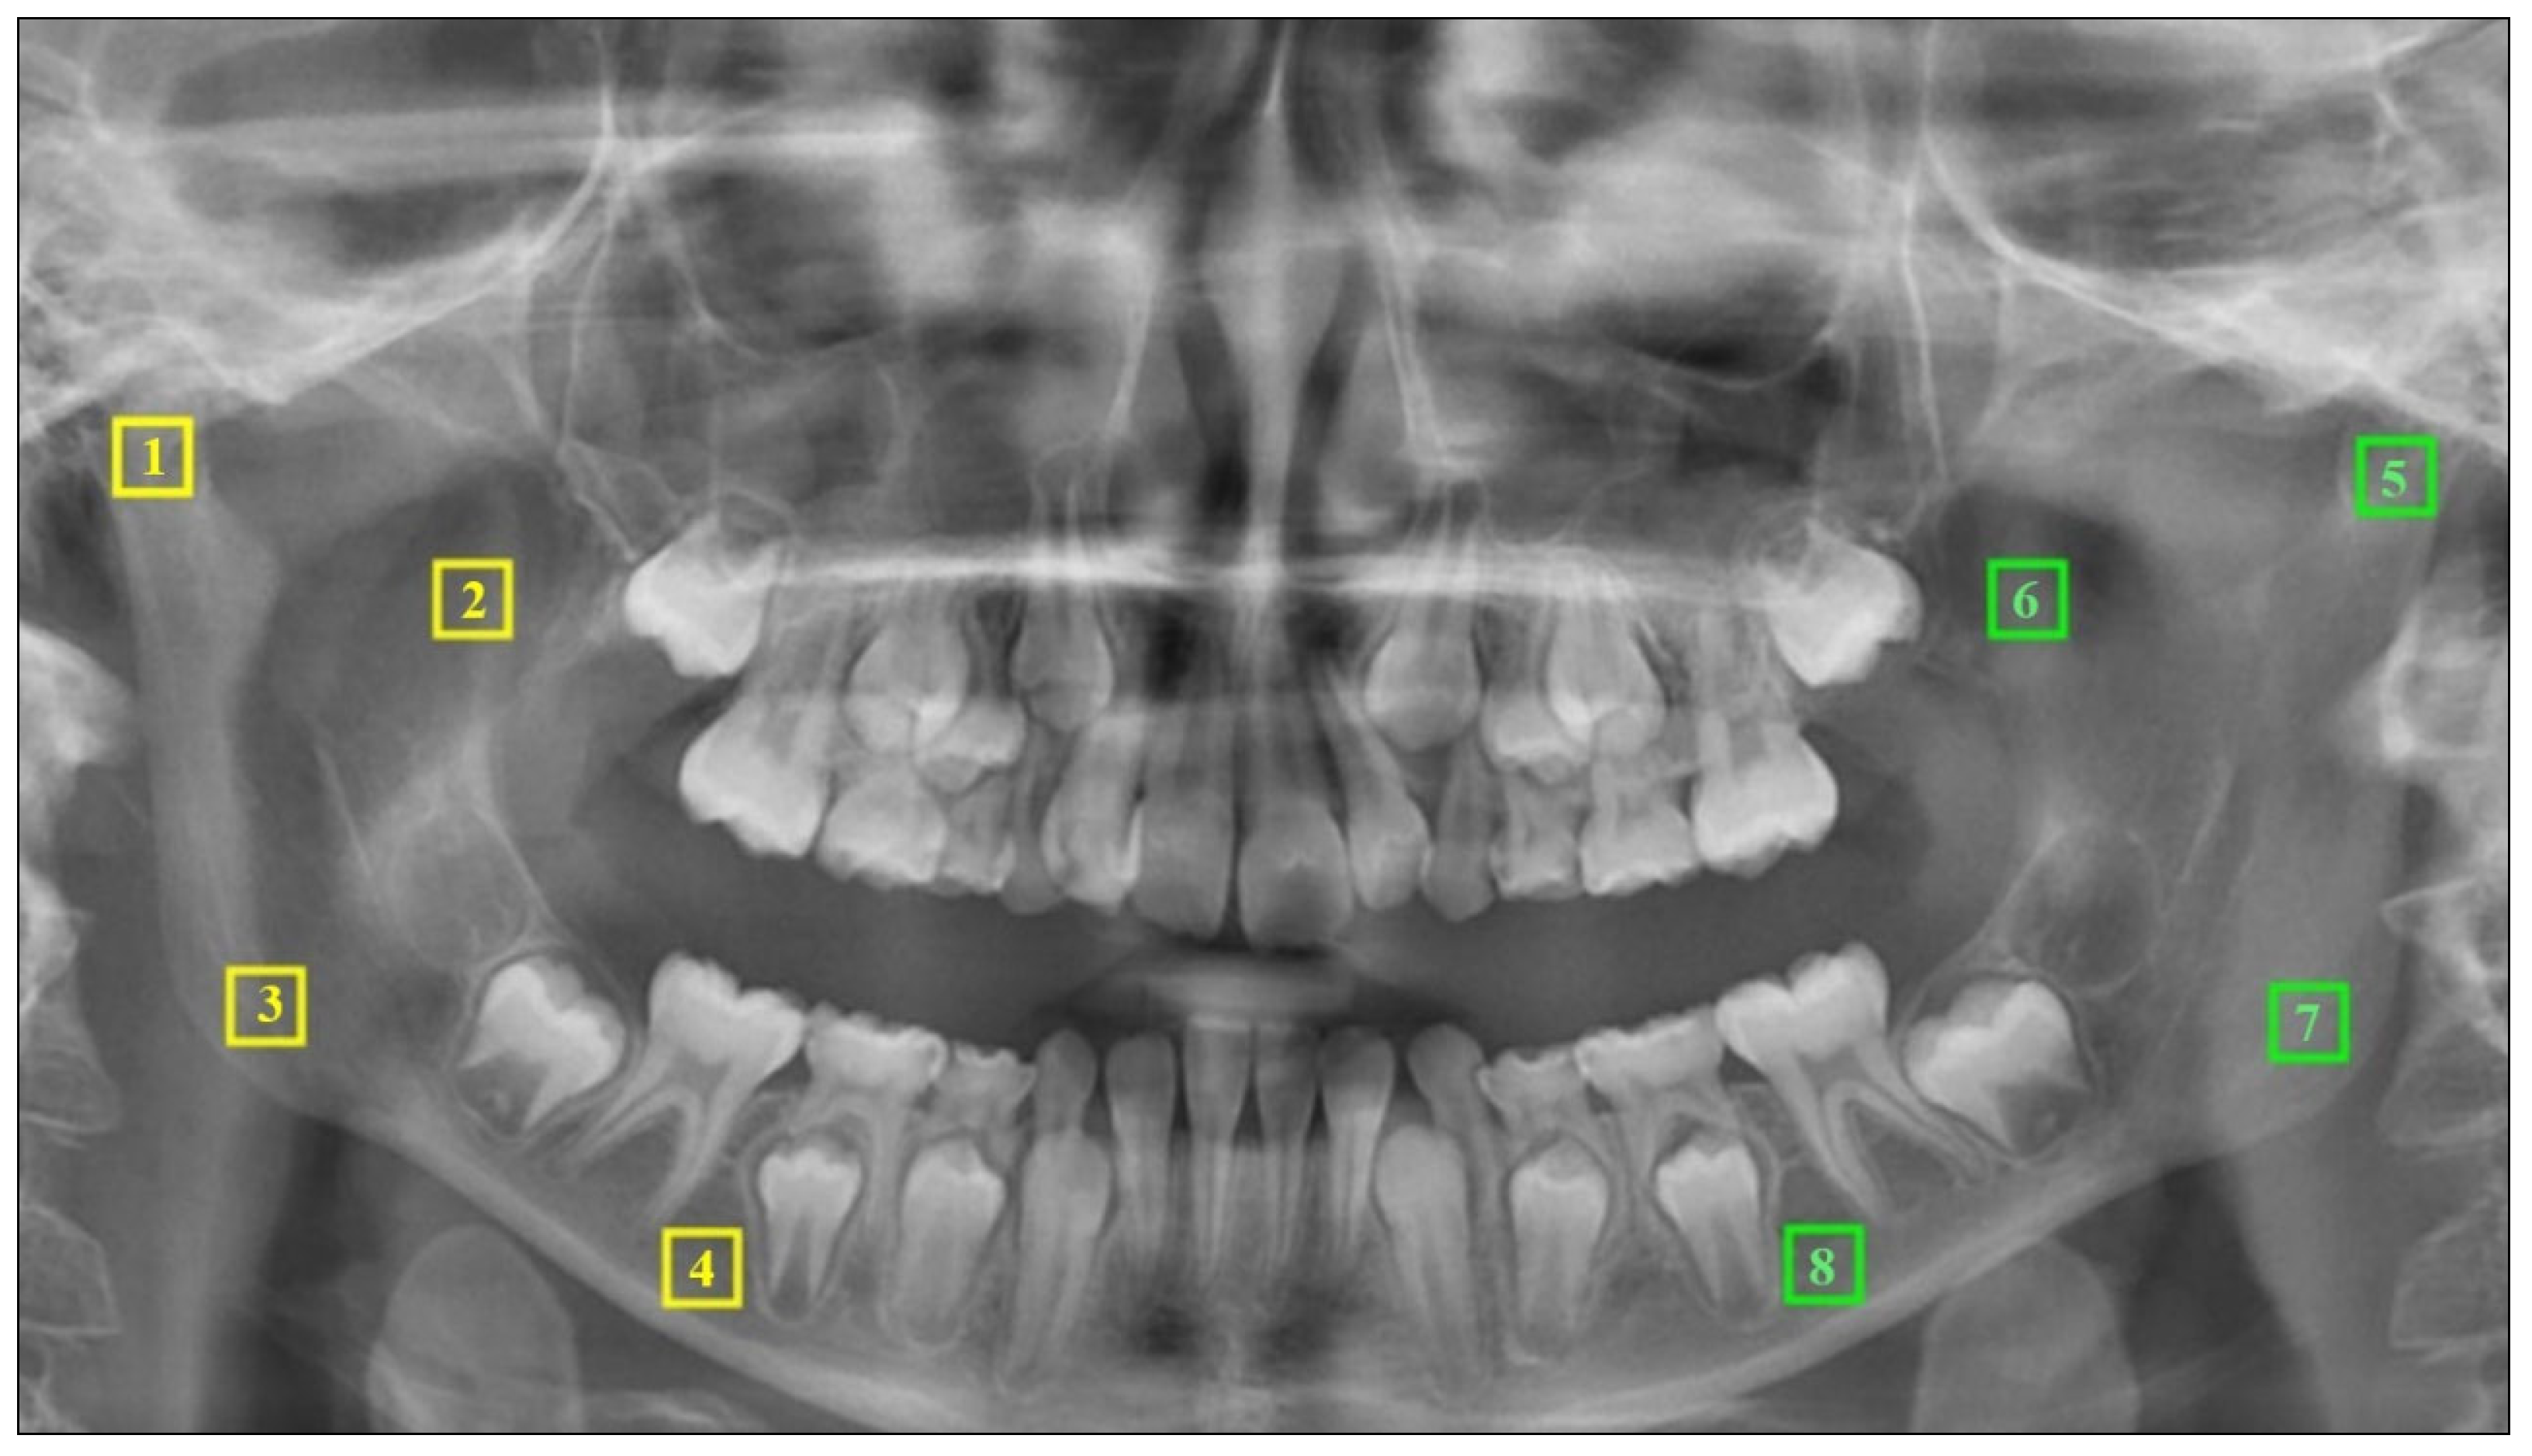

2.4. Fractal Analysis

3.1. Intra-Group and Inter-Group Comparison Results by Measurement Regions

3.1.1. For Mandibular Condyle

3.1.2. For Mandibular Angulus

3.1.3. For Mandibular Corpus

3.1.4. For Mandibular Coronoid